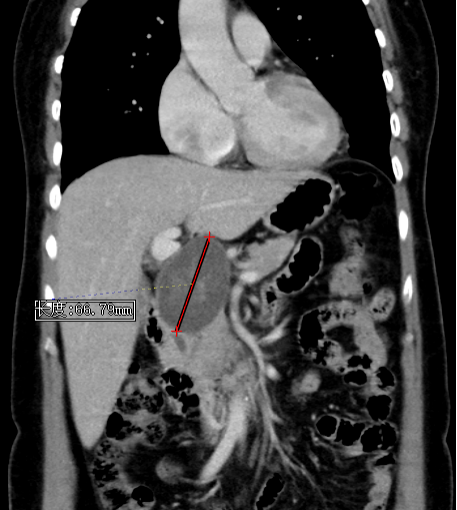

患者为76岁男性,因“身目黄染1周余”入院。入院后完善相关检查示肝功能异常,胆红素升高,增强CT及增强MR检查结果示胆总管下段梗阻,胆管壁增厚,考虑炎症与肿瘤相鉴别,进一步完善PET-CT检查后考虑胰头癌并压迫胆总管下段。

PET-CT示胰头结节(红色箭头),FDG代谢增高,考虑为恶性病变